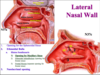

What is the major arterial supply to the posterior 2/3 of the nasal cavity?

Sphenopalatine artery, through its 2 major branches:

1) Posterior Lateral Nasal artery

2) Posterior Septal artery